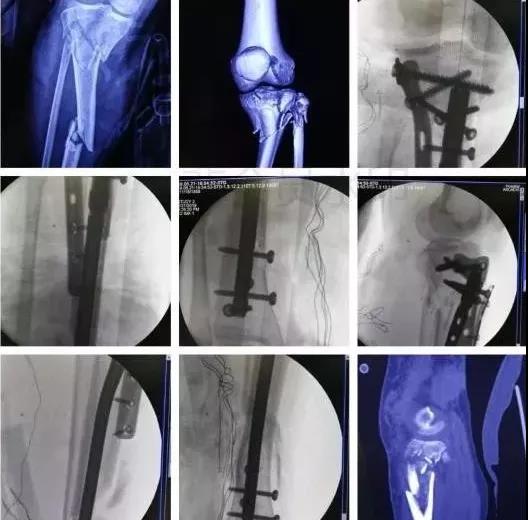

3)股骨远端骨折

- 开放性骨折,伤及腘动脉,坐骨神经,紧急手术,超膝关节外支架。

- 单纯闭合骨折,内固定:钢板或逆行髓内钉。

5)胫骨近端骨折(平台)

- 确定损伤机制,暴力损伤程度。

- 排除骨筋膜室综合征及血管,神经损伤。

- 高能量损伤,皮肤软组织条件差的,应延期手术。